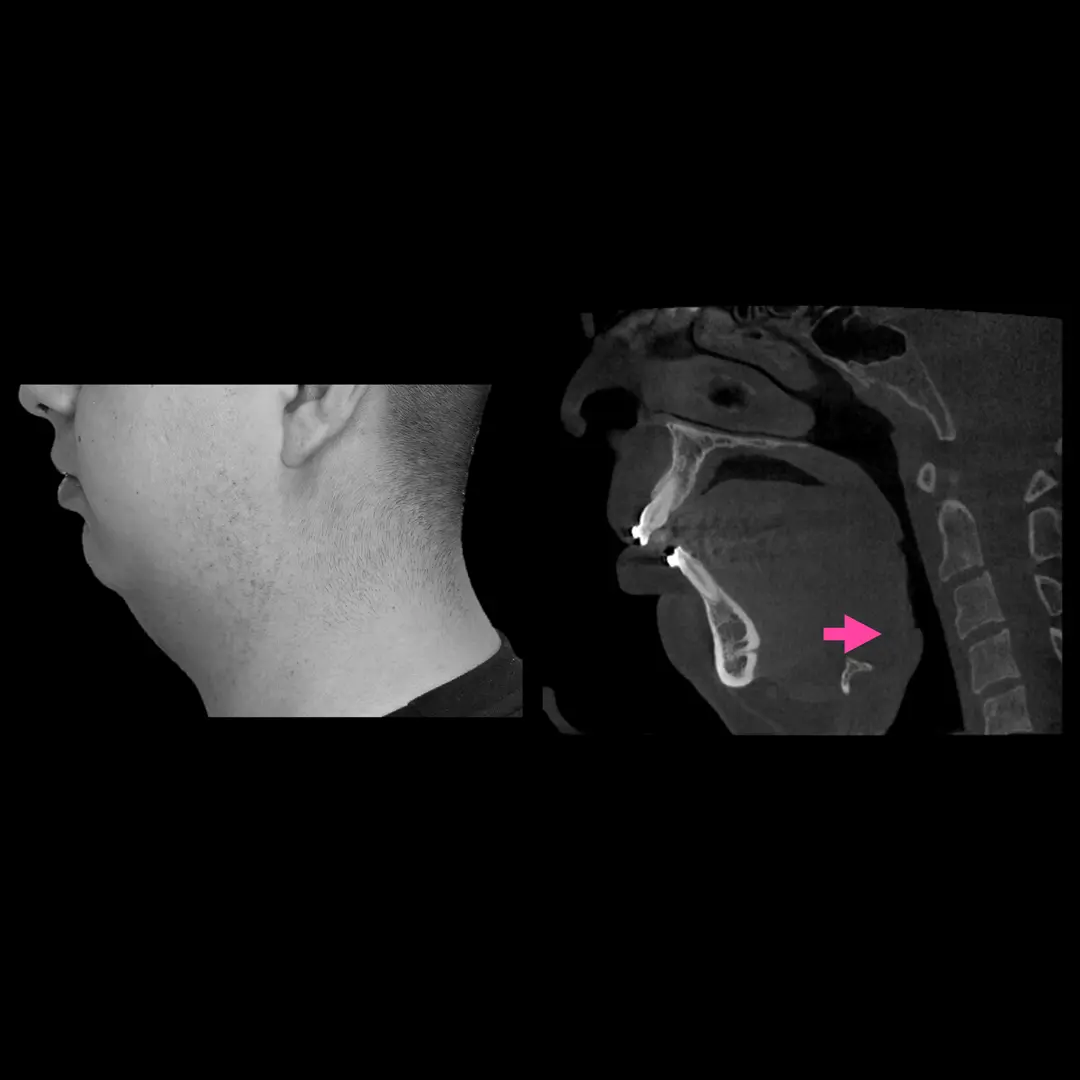

Hiperplasias o hipoplasias condilares

Es una enfermedad rara que se considera un crecimiento patológico y progresivo de uno o ambos cóndilos mandibulares, cuanto más grave es la patología, mayor asimetría y maloclusión desarrolla, que no solo afecta al desarrollo, masticación, deglución, habla, etc. si no que además esta particular entidad afecta altamente al individuo en un nivel psicosocial.